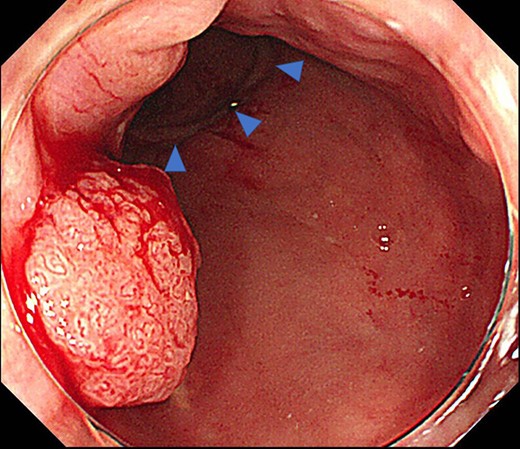

Case 1 was a 71-year-old man with a BMI of 29.7 kg/m2. Laparoscopic low anterior resection (LAR) and ileostomy was performed for rectal cancer in 2017 years. Postoperative fever and lower abdominal pain were noted, and colonoscopy was performed, and anastomotic leakage was noted with a correction of about 1/2 around the 6 o’clock direction of the anastomotic region, and fistula and formation of a large abscess cavity. After identification (Fig. 1), a tube was inserted for drainage and conservative treatment was performed. The patient was discharged on POD 46. Four months after the operation, marked improvement in the abscess cavity was noted but still remained (Fig. 2a and b). Anastomotic leakage was almost improved by colonoscopy at 17 months after surgery, but at the preference of the patient we performed colostomy 22 months after surgery (Fig. 3). It took a long time to improve intestinal movement of the colon because the large intestinal tract had not been used for a long time, and conservative treatment was performed using a nasogastric tube for paralytic ileus. Diet was initiated 7 days after surgery, and the patient was discharged from the hospital 14 days after surgery. The Wexner score [2] was 19 points one month after closure, 17 points 3 months after the operation and 16 points after 6 months after the operation, and severe anal dysfunction was observed, but gradually improved.

Colonoscopy revealed a true lumen (circle), an anastomotic site (triangle) and a cavity due to suture failure (arrow).